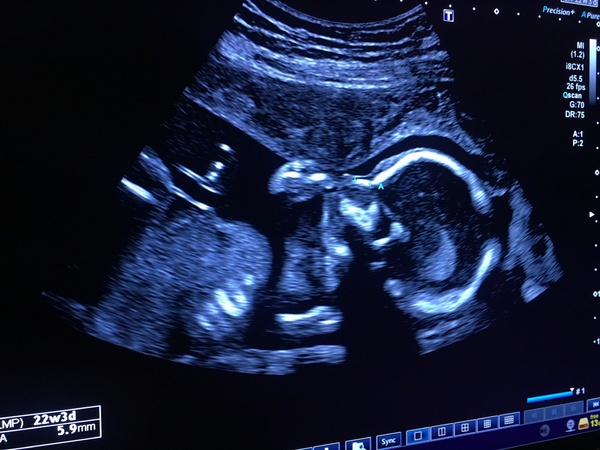

Nightmanagerfan · 23/11/2018 10:34

Oh and we had our “20 week” anomaly scan on Monday - all looking healthy! Baby slept throughout. I found it pretty tough as the combination of lying on my back and being poked for 45 mins (we are part of a research project so they do extra scans including a separate cardiology scan and an internal) was a bit much and I felt quite faint and sick. But worth it to see this little one sucking his/her thumb!

Your scan is gorgeous by the way! So clear and how lovely to capture baby sucking their thumb!